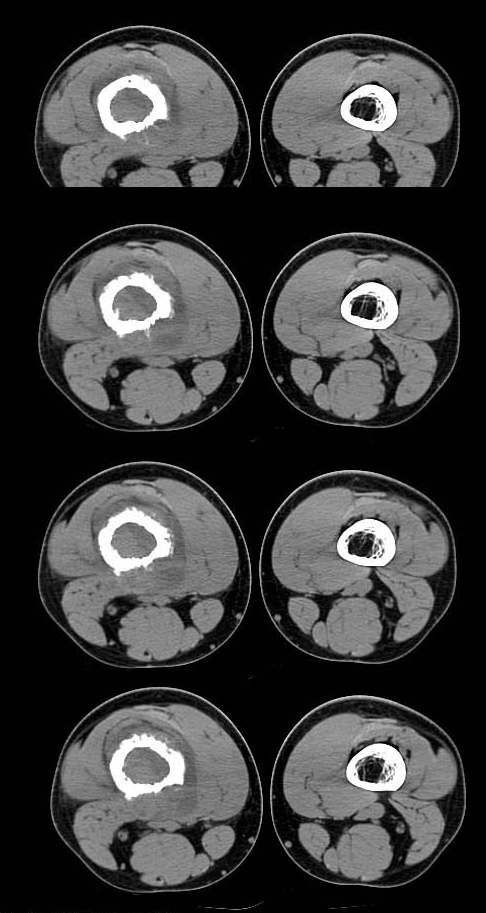

20岁,男,右股骨下端疼痛一个月,无发热,白细胞正常,皮肤不红,肿胀,触痛。

右股骨下端很长范围内的髓腔扩大,骨小梁破坏消失,皮质亦呈融骨性破坏,周围脂肪层次紊乱,肌肉受累及密度减低。考虑为:恶性骨肿瘤。请专家们分析骨肉瘤及尤文氏肉瘤的ct征象。

长骨ct见的较少,该病例股骨下端表现为边缘模糊的溶骨性破坏,伴有费用性脱钙,髓腔密度增高,呈毛玻璃样改变,病变周围软组织肿胀,脂肪间隙模糊,无骨膜反应,应密切结合临床,考虑骨纤维肉瘤或慢性骨脓肿。期待结果。

此病例基本可定是恶性骨肿瘤:髓腔内长范围肿块、皮质不规则破坏、软块及软组织浸润、瘤骨及不规则骨膜反应等。可以肯定地除外炎性病变和骨纤。

结合临床还是将尤文氏肉瘤放在前面,骨肉瘤不排除。纤维肉瘤及恶纤组多见老年人,不放在首要诊断范围内。